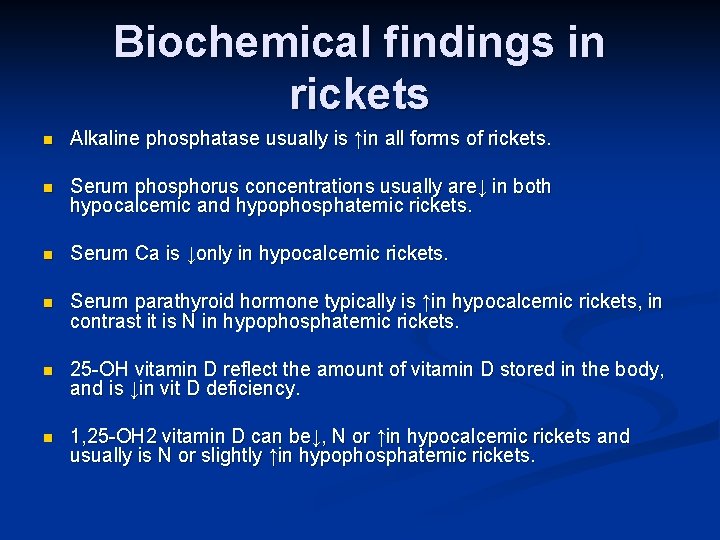

Biochemical findings in rickets n Alkaline phosphatase usually is ↑in all forms of rickets. n Serum phosphorus concentrations usually are↓ in both hypocalcemic and hypophosphatemic rickets. n Serum Ca is ↓only in hypocalcemic rickets. n Serum parathyroid hormone typically is ↑in hypocalcemic rickets, in contrast it is N in hypophosphatemic rickets. n 25 -OH vitamin D reflect the amount of vitamin D stored in the body, and is ↓in vit D deficiency. n 1, 25 -OH 2 vitamin D can be↓, N or ↑in hypocalcemic rickets and usually is N or slightly ↑in hypophosphatemic rickets.

Biochemical findings of rickets n Vitamin D deficiency rickets Low- normal serum calcium level n Increased secretion of PTH (secondary hyperparathyroidism) to compensate for low calcium n Hyperparathyroidism will increase renal excretion of phosphate, leads to low serum phosphate level n Elevated alkaline phosphatase enzyme n Reduced urinary calcium level n Low level of both 25 and 1, 25 - di hydroxy n

Biochemical findings of rickets Hypophosphatemic rickets n Low serum phosphate level n Normal calcium level n Normal parathyroid hormone level n High alkaline phosphatase level n In-appropriate low or normal 1, 25 -di hydroxy vitamin D n phosphate is the major stimulus for 1 hydroxylase